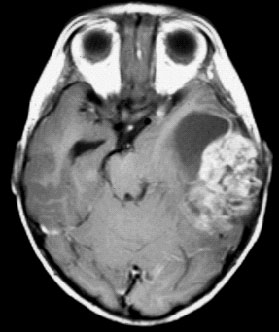

Cha Brain Tumor Imaging - Ucsfcme.com

Brain Tumor Imaging Soonmee Cha, M.D. Case 1 Cor & Axial T1-post Perfusion T2 Case 2 T1-post Case 3 Case 3 Case 4 T1-post ADCFLAIR DWI. 3.Abnormal recovery (aRec) baseline bolus recirculation T2*-weighted susceptibility signal time curve a b b x 100 a Peak height Percent ... Fetch Here